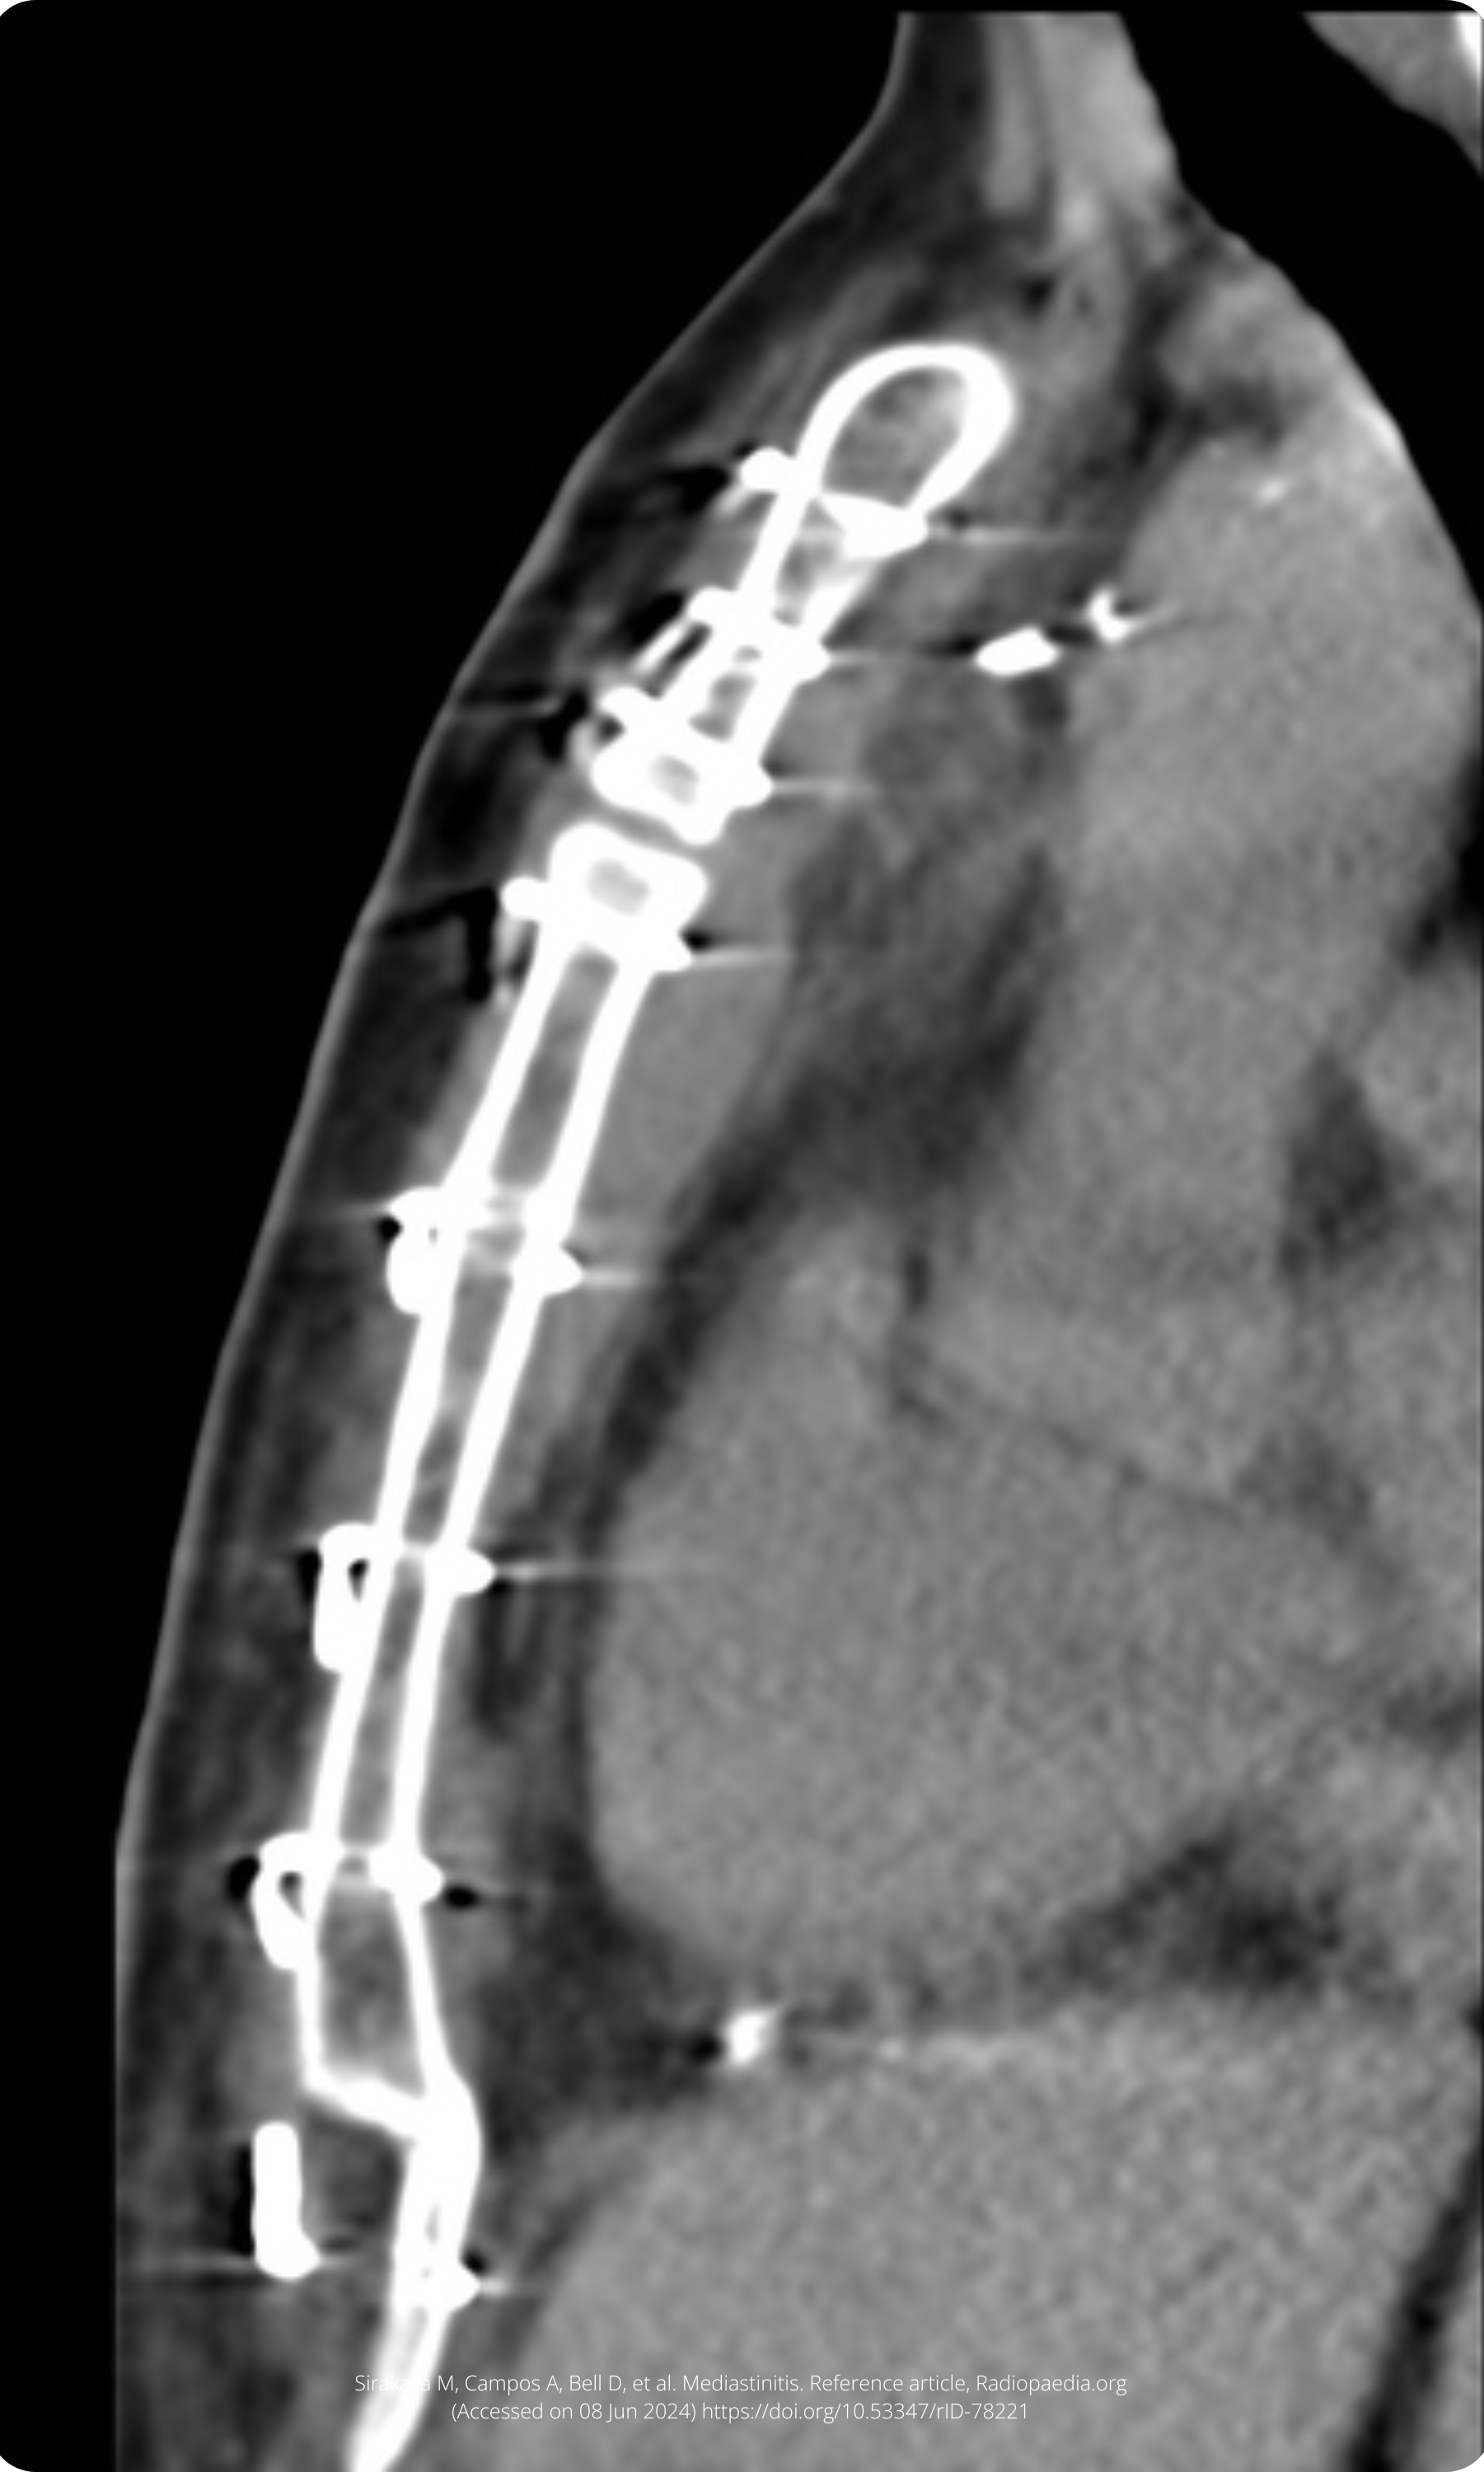

A 57-year-old lady presents with a sternal wound sinus 4 weeks after a median sternotomy for a mitral valve replacement.